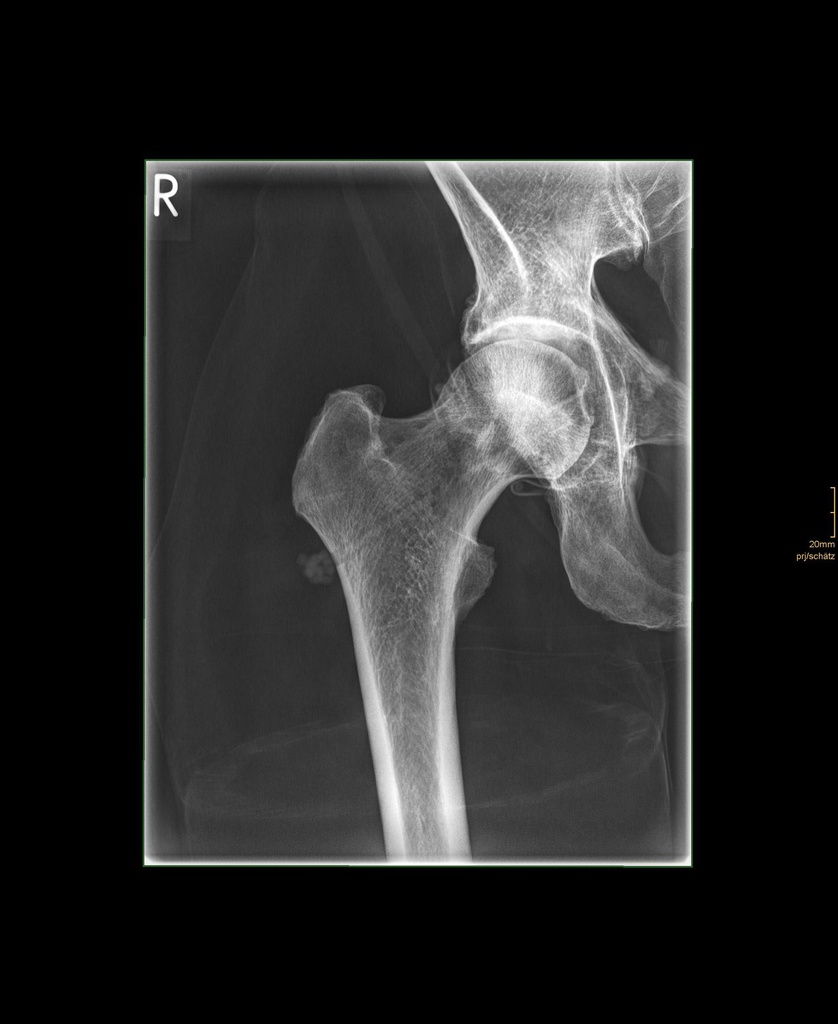

Dieses weltweit einmalige Phantom bietet erstklassige Übungsmöglichkeiten für die Lagerungs- und Einstelltechnik in der Projektions-Radiographie und gehört eigentlich zur Grundausstattung jeder Röntgen-Ausbildungsstätte. Das Phantom enthält ein natürliches menschliches Skelett sowie die Umrisse von Kehlkopf, Lunge, Herz und Nieren (Organe erscheinen als Schatten auf den Röntgenbildern), dadurch können mit dem Phantom echte Röntgenaufnahmen wie beim Patienten gemacht werden. Durch die Verwendung des echten Skeletts können Leitstrukturen im Knochen erkannt werden, was bei Kunststoffskeletten nicht möglich ist. Bei der Montage des Phantoms wird besonderer Wert auf die Darstellung der Gelenkspalte gelegt. Die Gelenke sind voll beweglich montiert, und ermöglichen die Lagerung in den normalen Röntgenpositionen (z.B. Froschposition, Pro- und Supination des Unterarms). Die Arme können nach oben bewegt werden, so dass das Modell auch für alle knöchernen Untersuchungen im CT verwendet werden kann. Bei jedem Phantom handelt es sich um ein handgefertigtes Unikat, welches sich in Größe und Ausführung unterscheiden kann. Je nach Modell können pathologische Befunde vorhanden sein, die äußere Erscheinung kann sich je nach Größe des Modells unterscheiden. Die neue Ausführung dieses Modells wurde in Zusammenarbeit mit einer namhaften deutschen Schule für Med. Techn. Radiologieassistenten komplett überarbeitet und erfüllt alle Anforderungen für die Ausbildung. Der Verkauf dieses Phantoms erfolgt nur gegen Nachweis der medizinischen Verwendung. Natürliche Größe.